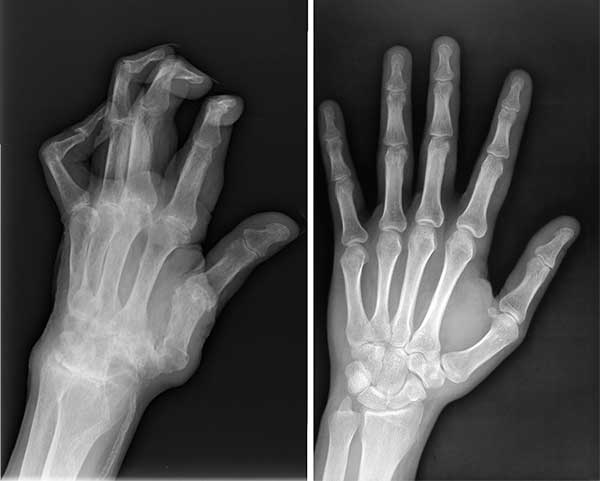

ตอนไปพบหมอครั้งแรก หมอใช้เวลานานมากในการดูภาพเอ็กซ์เรย์ แล้วบอกว่าให้ฉันเลิกทำงานหนักๆได้เลย และห้ามยกของหนักเกิน 2 กิโลกรัม

ไม่ใช่แค่หนูคนเดียวที่รอดเพราะผลิตภัณฑ์มหัศจรรย์ตัวนี้ สามีหนูป่วยเป็นโรคข้ออักเสบ ปลายนิ้วเสียหายมาก หนูเลยซื้อ Flexabon ให้เขาทาน พวกเราทานด้วยกันแล้วก็หายกันทั้งคู่เลยค่ะ